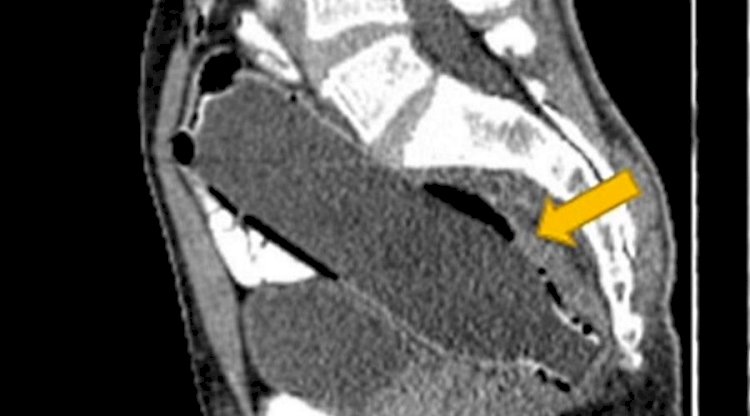

Somente após a tomografia computadorizada ficou constatado, pelo formato do objeto, o que tinha acontecido. O caso foi publicado, sem identificar o paciente, na revista Clinical Case Reports.

Após o exame, ele contou que inseriu a garrafa, imaginando que conseguiria retirá-la segurando a tampa. Mas, não conseguiu puxar o objeto, ficando alojado completamente em seu intestino grosso.